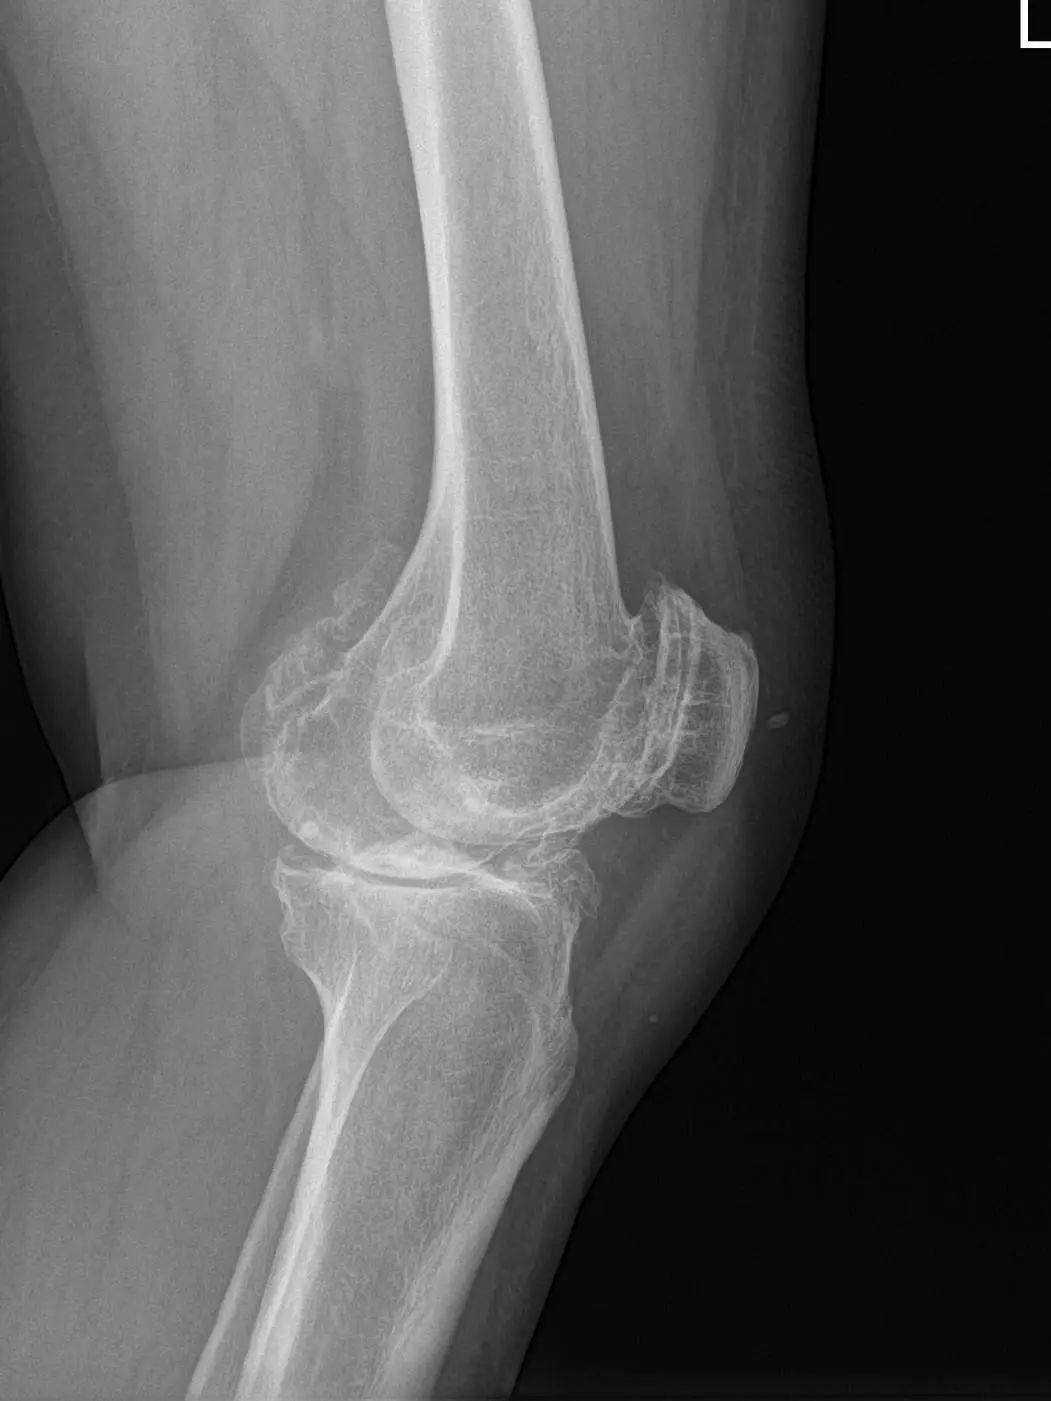

67岁的邵阿姨,双膝关节疼痛10余年,疼痛主要集中在屈伸膝关节时髌骨下。长期口服及外用药物治疗效果欠佳,反复加重,双膝的x线检查提示主要为髌股关节的退行性骨关节炎。程飚主任结合患者症状,影像学结果,体格检查,发现邵阿姨主要问题集中在髌股关节,膝关节间隙,内外侧髁,胫骨平台均可,为解决邵阿姨痛苦,尽可能保留关节,程飚主任决定对邵阿姨进行双侧膝关节的髌股关节表面置换,截骨量较少,邵阿姨第二天就能下地活动了,屈伸关节也不痛了,对手术疗效表示非常的满意。

部分膝关节置换手术目前已是非常成熟的治疗方法,亦属于保膝治疗的一种。主要包括单髁置换,髌股关节置换。单髁置换主要把膝关节内侧髁或者外侧髁表面已经磨损的部分替换成金属的假体和高分子聚乙烯耐磨垫片。髌股关节置换主要把髌股关节表面已经磨损的部分替换成金属的假体。

病变局限于髌股关节的患者,可行髌股关节表面置换;